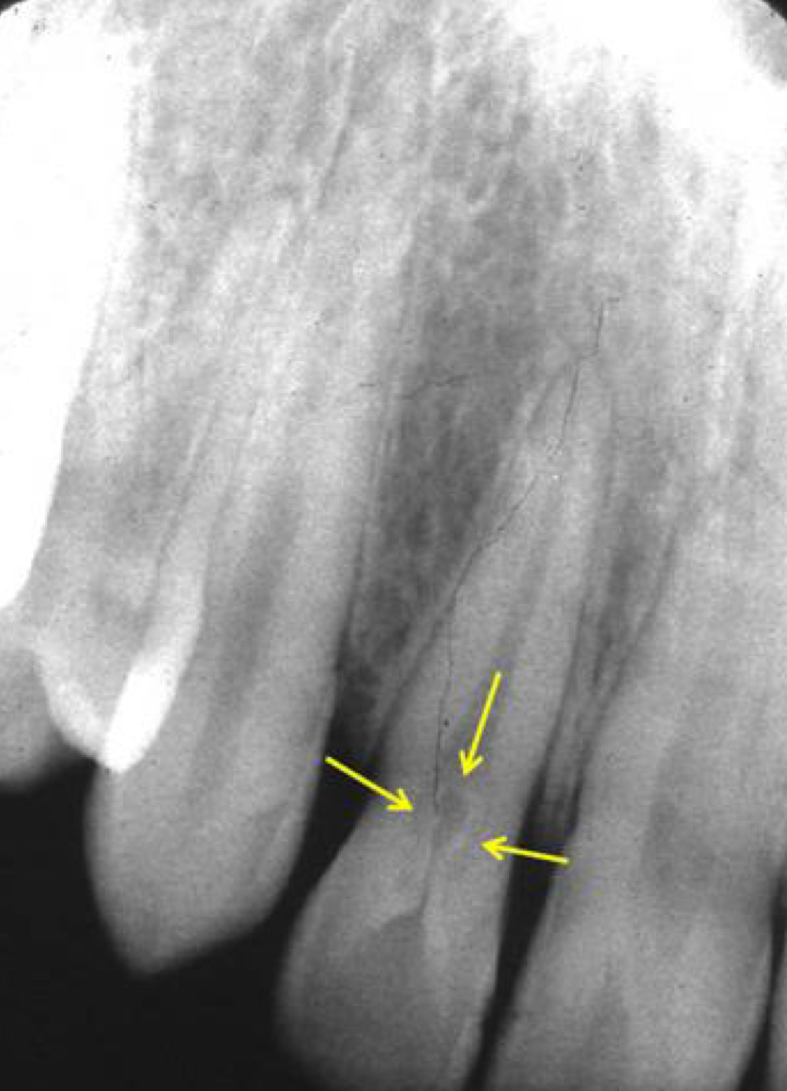

What are dilacerations?

Sharp curve in root suggest trauma or bony interference during root formation